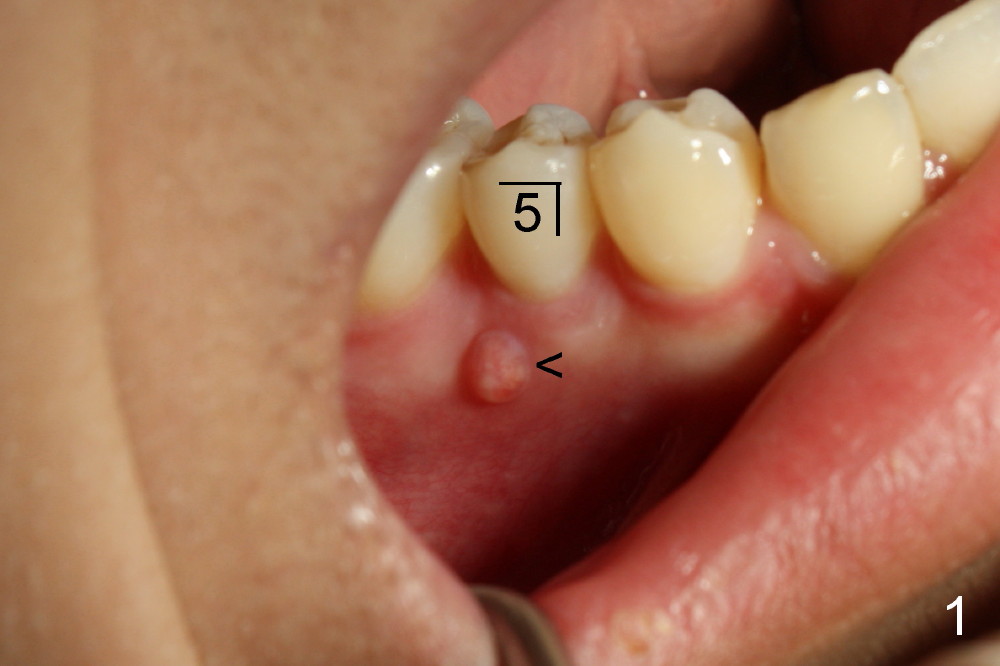

上集发表时,还没有见到病人,这集回答卢红医师疑问(下面)。今天病人来诊所诊治,他没有任何症状,右下五号牙根尖瘘道(图一箭头)是以前牙齿矫正医生发现的,咬合面中央隆起(图二箭头),后者中心好像有个小开口。对侧仿佛没有同样病变(图三*:左下五)。按照方柄忠大夫建议,根管治疗前做活力测试(Endo Ice):右下五的确死髓,有轻度扣痛。

治疗前告诉病人,如果治疗后瘘道不消失,可能需要进一步治疗(根尖切除术)。根管开口(Access)如图二插图表示,唯一不理解的是这个牙齿只有一个根管,似乎偏向颊侧,扩大针尽量往舌侧拉,颊舌侧之间好像有狭部感觉(Isthmus)。Apex Locator运转正常,说明根尖关闭。预先弯曲扩大针:10-20号,然后使用40/.06 rotary file,太容易达到根尖,所以逐步使用扩大针治七十号,但是逐渐失去working length (WL),最后七十号牙胶尖插不到根尖(图四(箭头:根尖阴影)),而40/.06牙胶尖在有冲洗液下容易达到WL,接触(Binding)不够紧密,好像再大一号扩大针(四十五号)就达到不了WL。由于时间问题,使用AH26 Plus Paste,主牙胶尖40/.06,以及medium and fine medium accessory gutta percha(各一根)完成充填(图五),最后树脂充填,不准备做牙冠,观察。